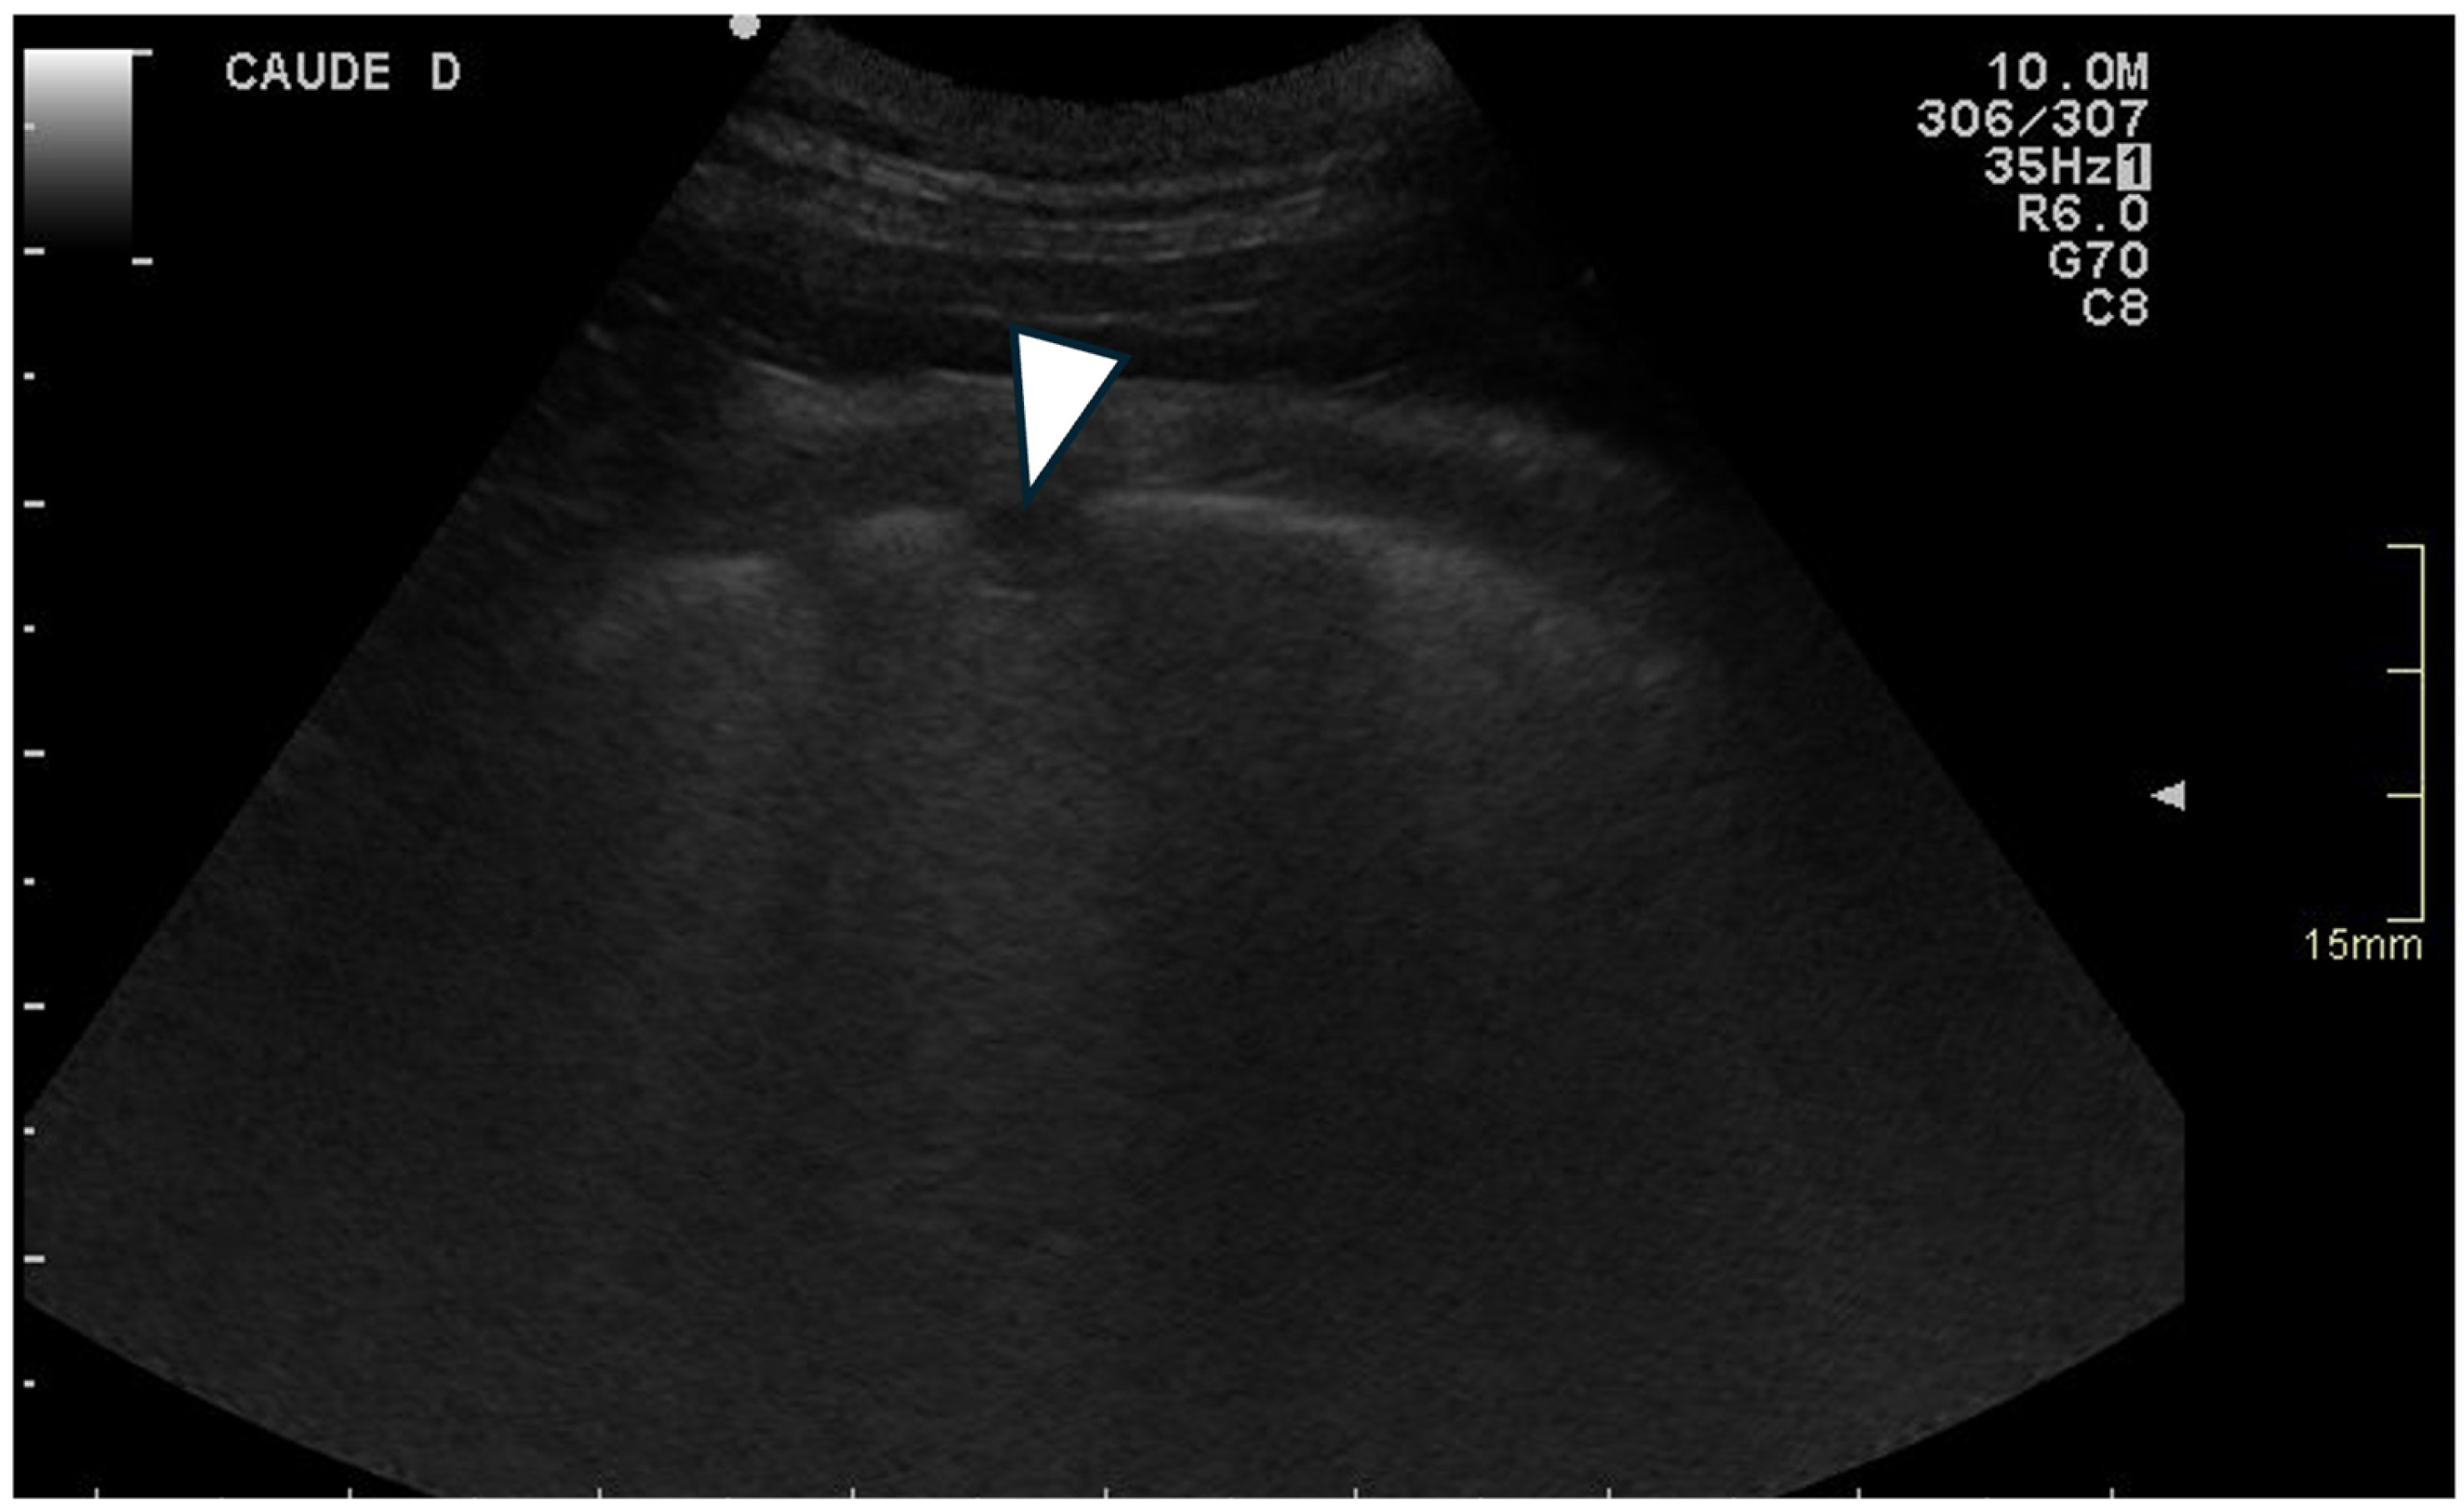

2.1. Thoracic Ultrasonography

3.3.3. Ring-Down Artefacts

3.3.4. Pleural Surface